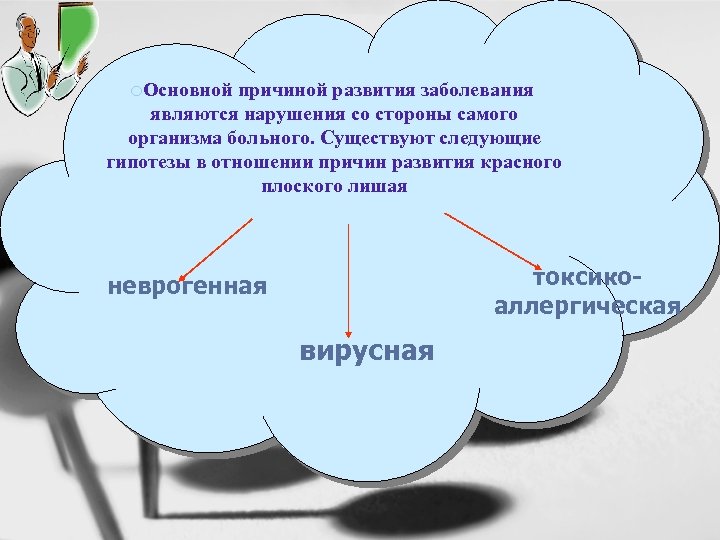

¡Основной причиной развития заболевания являются нарушения со стороны самого организма больного. Существуют следующие гипотезы в отношении причин развития красного плоского лишая токсико аллергическая неврогенная вирусная